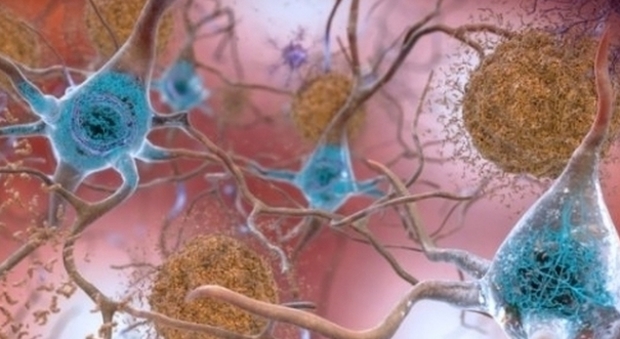

La nuova formulazione al litio è stata quindi applicata a un modello transgenico di ratto che esprimeva le proteine mutate umane tipiche dell’Alzheimer, un modello animale che i ricercatori avevano creato e caratterizzato. Questo ratto sviluppa caratteristiche della malattia di Alzheimer umana, tra cui un progressivo accumulo di placche amiloidi nel cervello e concomitanti deficit cognitivi.

Incoraggiati da questi risultati precedenti, i ricercatori hanno deciso di applicare la stessa formulazione di litio nelle fasi successive della malattia, ai loro ratti transgenici che modellano gli aspetti neuropatologici della malattia di Alzheimer. Questo studio ha scoperto che i risultati benefici nella riduzione della patologia e nel miglioramento della cognizione possono anche essere raggiunti in fasi più avanzate, simili a fasi precliniche tardive della malattia, quando le placche amiloidi sono già presenti nel cervello e quando la cognizione inizia a declinare.